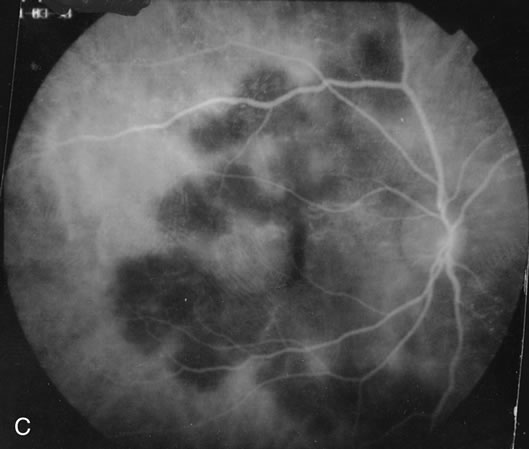

Some patients present with subretinal bands that extend between chorioretinal scars. In addition there may be initial active yellow choroidal lesions that subsequently become atrophic. Vitreous cells are usually present although they may be few and difficult to detect. Visual acuity loss in these cases may be due to active choroidal neovascularization, subretinal bands under the fovea, or from cystoid macular edema. The vast majority of affected patients are women with a mean age of 27 years and both eyes are usually involved. The affected individuals tend to be myopic.49 The age range is from 6 years to 76 years and there is no racial predilection.40 Whether it is a separate disease or a more severe form of multifocal choroiditis is controversial (Figs. 10 and 11). Aggressive therapy is warranted because it has a poorer prognosis than most cases of multifocal choroiditis. This syndrome has been called either diffuse subretinal fibrosis or progressive subretinal fibrosis syndrome.

Fig. 10. A. Fundus photograph showing the subretinal fibrosis extending from the disc to the periphery in a case of diffuse subretinal fibrosis. B. Fundus photograph showing the marked fibrosis in the midperiphery. C. Multifocal choroiditis type lesions noted in the inferior retina.